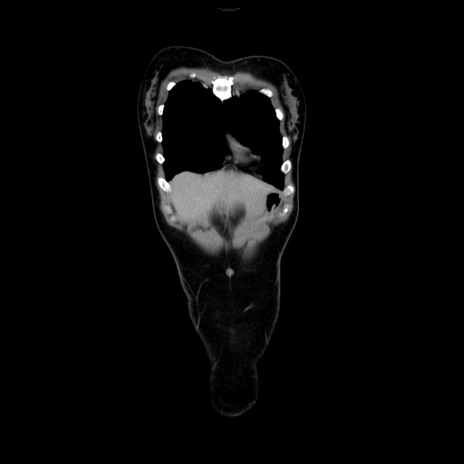

MRI(4日後)